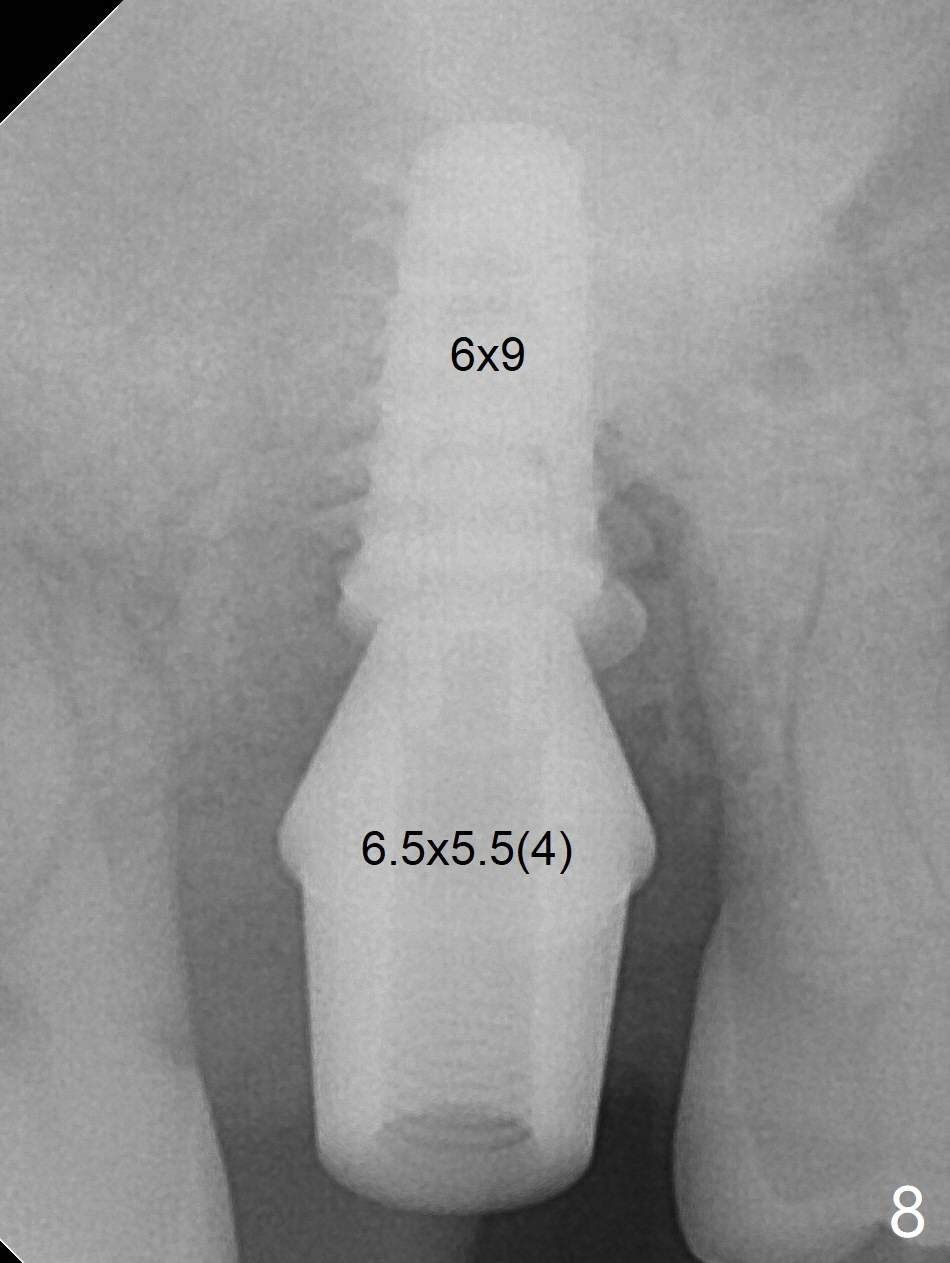

When a 6x9 mm IBS implant (definitive) is placed with a 6.5x5.5(4) mm abutment, they are seated too deep for provisional (Fig.8). The implant/abutment are removed and replaced by a 6.5x11 mm one in a shallower position; after trimming the same abutment as mentioned above (Fig.9), an immediate provisional is fabricated to keep bone graft in place. The coronal threads of the implant are covered with bone 6 months postop (Fig.10).